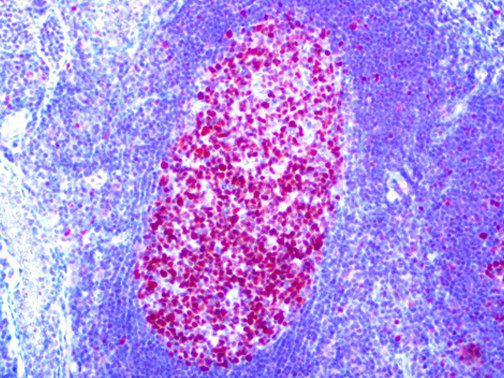

It is the ICU physician who is most likely to witness one of the deadliest manifestations of the abnormal immunological response, the cytokine storm syndrome (CSS). This response is also referred to by some as the cytokine release syndrome (CRS). CSS is characterized by continuous activation and expansion of macrophage and lymphocyte populations, which secrete large amounts of cytokines, causing the cytokine storm. This massive cytokine release is akin to hemophagocytic lymphohistiocytosis (HLH) disease, a syndrome characterized by initial unchecked and persistent activation of cytotoxic T lymphocytes and NK cells.

Clinical and laboratory manifestations of HLH include fever, enlarged liver and/or spleen, neurologic dysfunction, coagulopathy, liver dysfunction, cytopenias (i.e., low levels of erythrocytes, leukocytes, and/or platelets), hypertriglyceridemia, hyperferritinemia, hemophagocytosis, and eventually diminished NK cell activity as the immune system becomes progressively paralyzed. HLH can be familial (primary HLH) or secondary to another disease process (sHLH), such as rheumatic disease, in which it is referred to as macrophage activation syndrome (MAS, characterized by elevated ferritin).